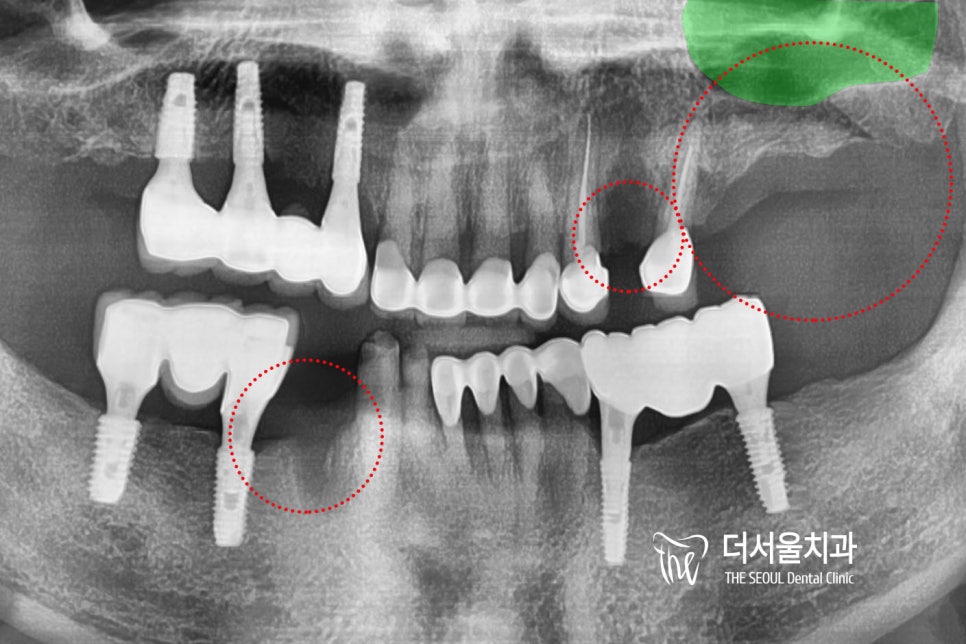

안녕하세요, 글쓴이 박현준 원장입니다. 오늘은 상악동 거상술 및 뼈이식과, 같이 임플란트 수술을 진행했던 증례입니다. 아래 사진으로 바로 설명드릴게요.

안녕하십니까, 여러분! 더서울치과 박현준 원장입니다. 얼마 전, 이가 흔들려서 걱정이 된다며 다급한 모습으로 찾아오셨던 분이 계십니다. 오늘은 그분의